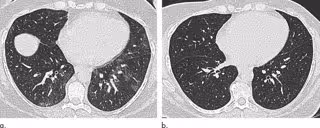

Los investigadores utilizaron la TC para medir el tamaño y la forma de la tráquea y evaluar el atrapamiento de aire, un fenómeno en el que el exceso de aire permanece en los pulmones después de exhalar, lo que resulta en una reducción de la función pulmonar. El atrapamiento de aire es un signo indirecto de obstrucción en las pequeñas vías respiratorias del pulmón.

Cuando los investigadores compararon los resultados al inicio y seis meses después de la cirugía bariátrica, encontraron que la cirugía y la pérdida de peso estaban asociadas con cambios morfológicos o estructurales en el pulmón y la tráquea.

La TC postoperatoria mostró reducciones en el atrapamiento de aire y una menor incidencia de colapso traqueal. El cambio en la extensión del atrapamiento de aire por TC fue el predictor más fuerte de mejoría en la disnea o falta de aliento.

"Por primera vez, este estudio ha demostrado cambios en la morfología de las vías aéreas grandes y pequeñas que mejoran cuando las personas pierden peso --señala Copley--. Estas características se correlacionan con una mejora en los síntomas del paciente".

Los resultados sugieren que puede haber un elemento reversible de inflamación de las vías respiratorias pequeñas relacionado con la obesidad y que la reversión de esta inflamación se correlaciona con la mejora de los síntomas. Los hallazgos también apuntan a la TC como un marcador potencial de esta inflamación.